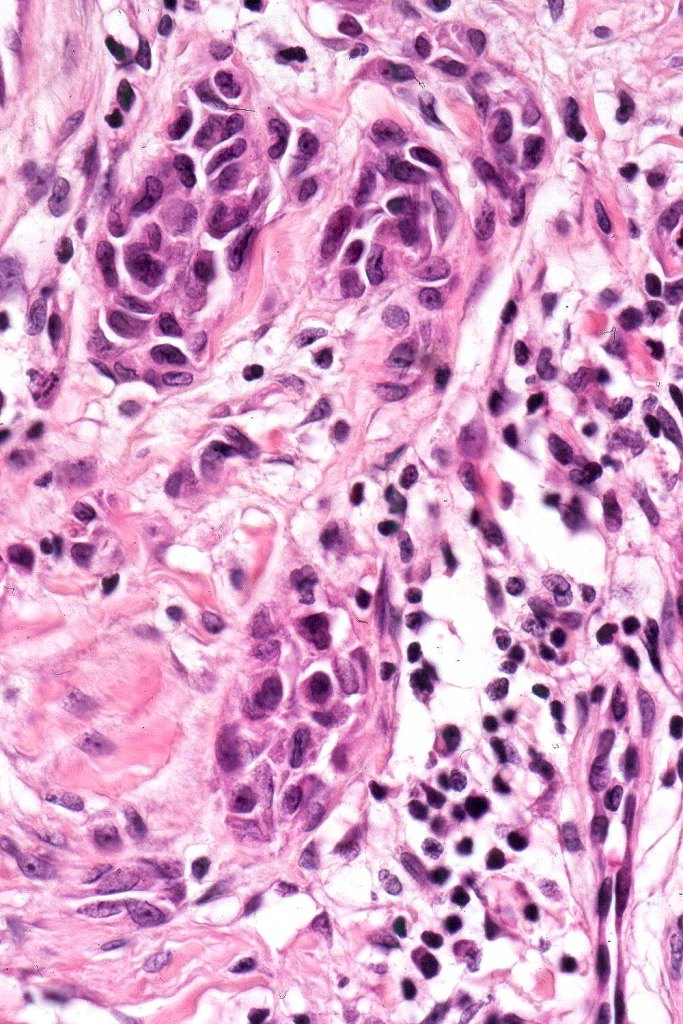

•Epithelioid cell variants often show greater pleomorphism and cells can frequently appear bizarre with abundant, sometimes ground glass cytoplasm and large vesicular nuclei with prominent eosinophilic nucleoli, multinucleate cells are often seen

•Intracytoplasmic pseudoinclusions commonly present in epithelioid cells

•Kamino bodies (often multiple) are a characteristic feature

•Lymphocytic infiltration at the base of the lesion